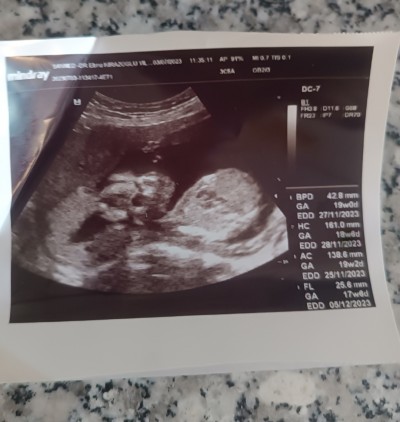

Kızlar ultrason kağıdından cinsiyet tahmini yapabilen varmı bide kaç haftalık olduğu anlayan varmı

Gebelik haftası 17

GA: 19 week, 0 day. Yani 19 hafta, 0 gün bebeğin haftası. Sağlıkla büyüsün inşallah.